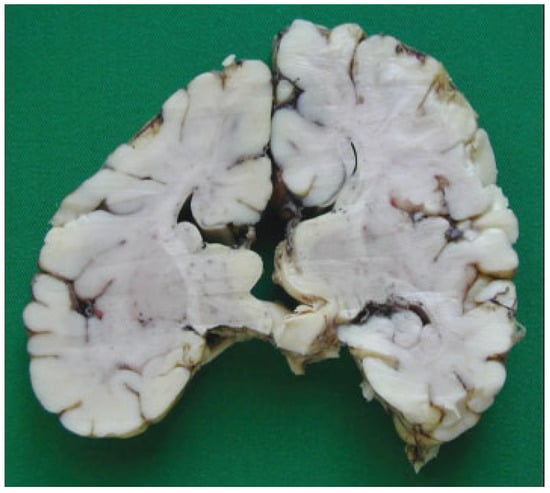

The autopsy study described a girl, 2 months and 20 days old, with karyotype (46,XX). She had frontonasal malformation (hypertelorism, broad nasal bridge, bifid nasal tip and anterior cranium), macrostomia, retrognathia, and bifid tongue. She also presented maxillomandibular bony fusion and fusion of the tongue to the palate and to the inferior lip by a hairy polyp (Figure 8), both corrected surgically. In the cranium, the sella turcica was broadened (Figure 9), with little prominence of the clinoid apophyses and with two cavities that contained two complete hypophyses with two infundibulums (Figure 10). The three cranial fossae were narrowed anteroposteriorly. The central nervous system (CNS) had both olfactory bulbs and corpus callosum agenesis (Figure 11 and Figure 12), anomalous morphology of the brain stem and spinal cord (Figure 13), and neuronal heterotopia in occipital white matter and leptomeningeal heterotopia.

Figure 12.

Corpus callosum agenesis.